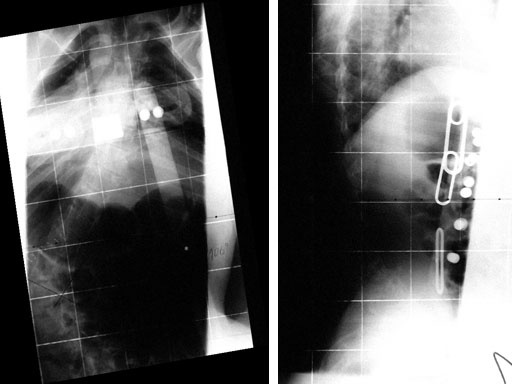

Case provided by Cornelius Wimmer, Vogtareuth, Germany

A 23-year-old man with neurogenic kyphoscoliosis, Cobb angle: 120. Fusion of T7S1 with universal reduction screws. Duration of surgery: 4.5 hours.